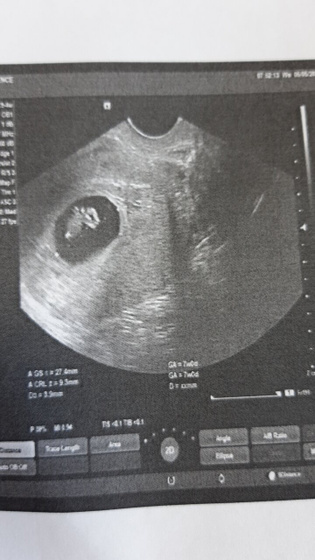

Малыш растет.На 6 н.6 дней размер плодного яйца 27 мм.Сердечко мерцает.

Еще раз внимательно исследовали на предмет внематочной вторым эмбрионом.Видимо он просто не имплантировался.

Следующее узи 20 мая.Будет ровно 9 недель.